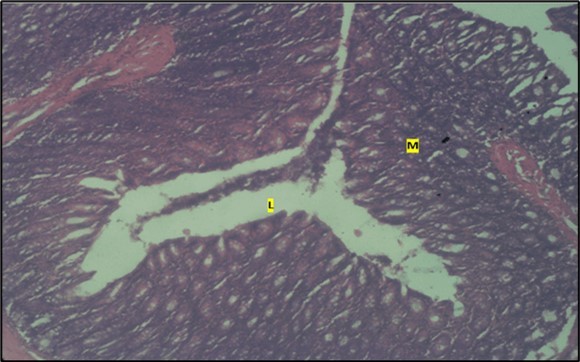

Micrographs of The Large Intestine

Results from the large intestine histological observation showed normal appearance of epithelial cells lining the mucosa with no pathological observations in control animals (Figure 5). However, administration of Abelmoschus esculentus at low dose showed dysplasia of cells and loss of normal epithelial shape (Figure 6) and the high dose group showed mild dysplasia (Figure 7)

Figure 5.Control showing the lumen (l), the epithelial cells lining the mucosa (m) appearing normal H & E. X40.

Figure 6.Low dose showing the lumen (l), smooth muscle layer (sm) and dysplasia of the mucosa (m). there is loss of epithelial shape H & E. X40.

Figure 7.High dose showing the lumen (l), the smooth muscle layer(sm). mucosa (m) shows mild dysplasia H & E. X40.